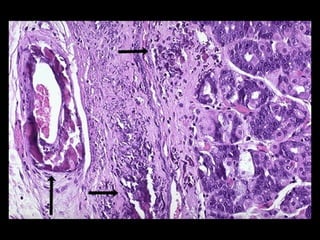

ACUMULACIONES PROTEICAS •- PROTEÍNASESTRUCTURALES : acumulación de prequeratina y otros filamentos intermedios en el citoplasma de los hepatocitos (cuerpos de Mallory) en la enfermedad hepática alcohólica . Acumulación de proteínas asociadas a microtúbulos y neurofilamentos en la enfermedad de Alzheimer (maraña neurofibrilar).- •- PROTEINURIA: reabsorción de proteínas en las nefropatías perdedoras de proteínas en los túbulos contorneados proximales .-

ACUMULACIONES PROTEICAS •- INMUNOGLOBULINAS:acumulación de inmunoglobulinas en el retículo endoplásmico de las células plasmáticas (cuerpos de Russell), probablemente por síntesis defectuosa o transporte inadecuado de las mismas.- •- ALFA-1-ANTITRIPSINA: en el retículo endoplásmico de los hepatocitos por déficit enzimático estructural .-